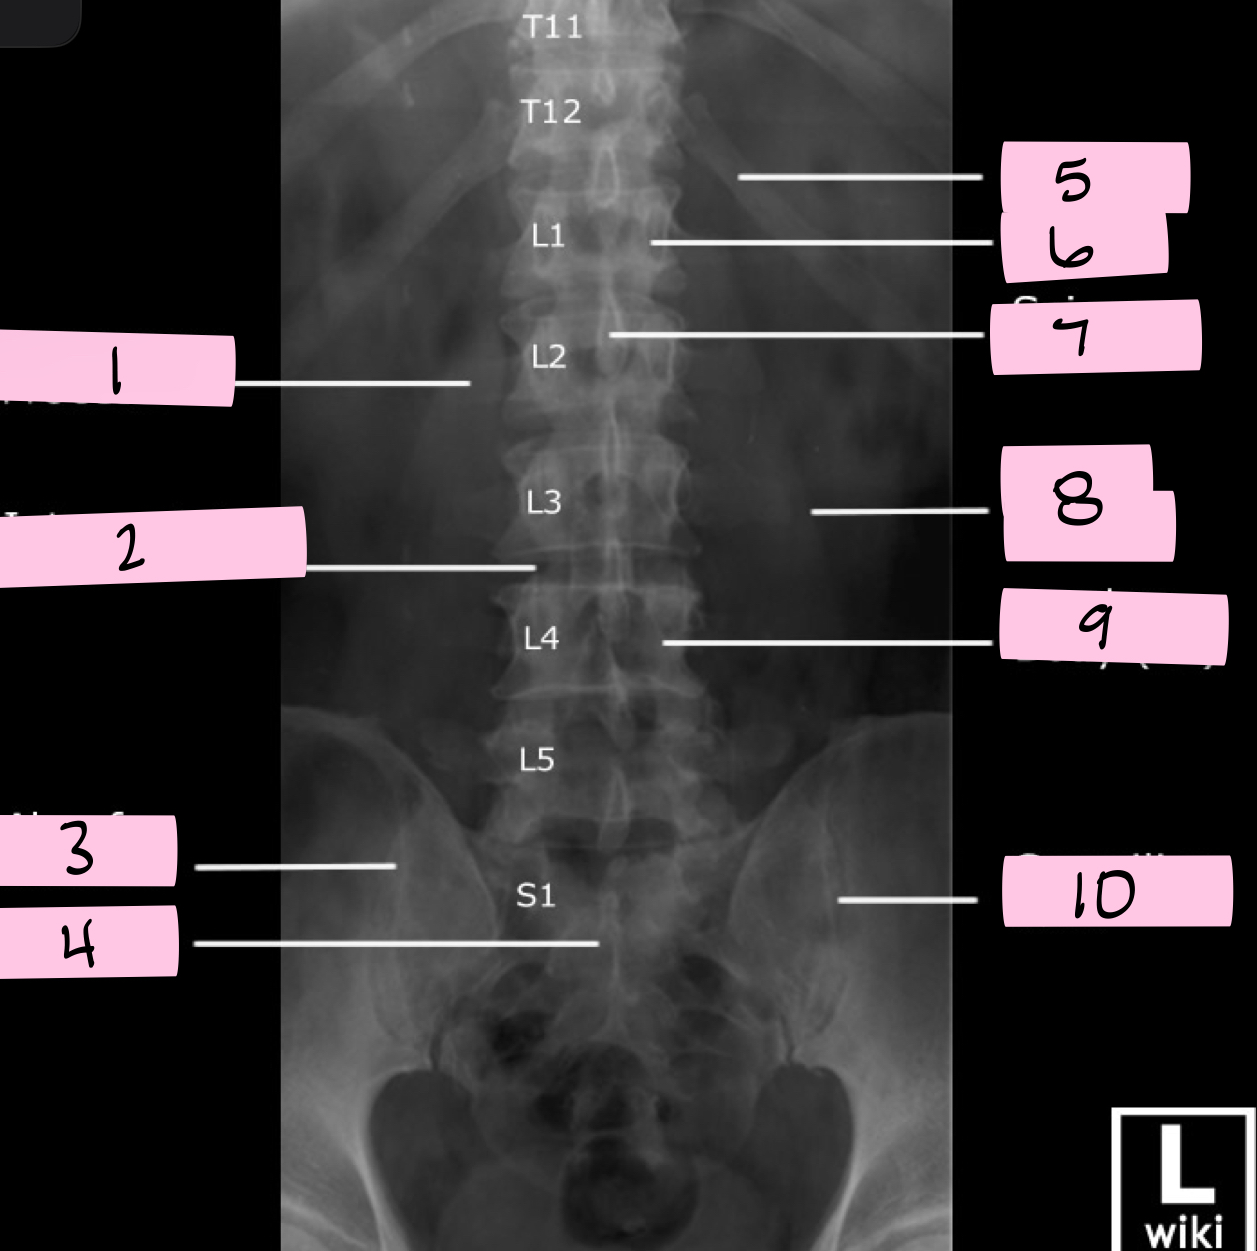

What is 1 pointing to?

Transverse process

What is 2 pointing to?

Intervertebral disk

What is 3 pointing to?

Ala of sacrum

What is 4 pointing to?

Sacrum

What is 5 pointing to?

12th Rib

What is 6 pointing to?

Pedicle

What is 7 pointing to?

Spinous process

What is 8 pointing to?

Psoas muscle

What is 9 pointing to?

Lumbar body (L4)

What is 10 pointing to?

Sacroiliac joint